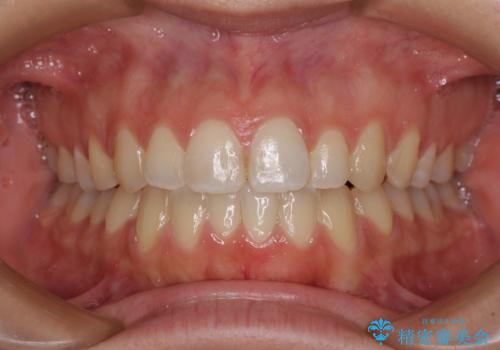

- 前歯の出っ歯と口元の閉じにくさを気にして来院された患者様です。

口元を積極的に引っ込めるために、上下左右の小臼歯4本を抜歯することとしました。

4本の歯を抜歯したことで、飛び出していた口元が引っ込み、横顔が大きく改善されました。

咬み合わせが悪化することのないようにスペースを閉じていくことができ、比較的スムーズに治療を進めることができました。